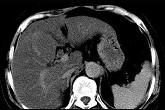

问题 男,32岁,肥胖,常酗酒,肝肋下一横指,肝区轻微压痛,影像表现如图,应诊断为 ( )

选项 A.肝炎 B.肝硬化 C.脂肪肝 D.肝豆状核变性 E.肝含铁血黄素沉着

答案 C